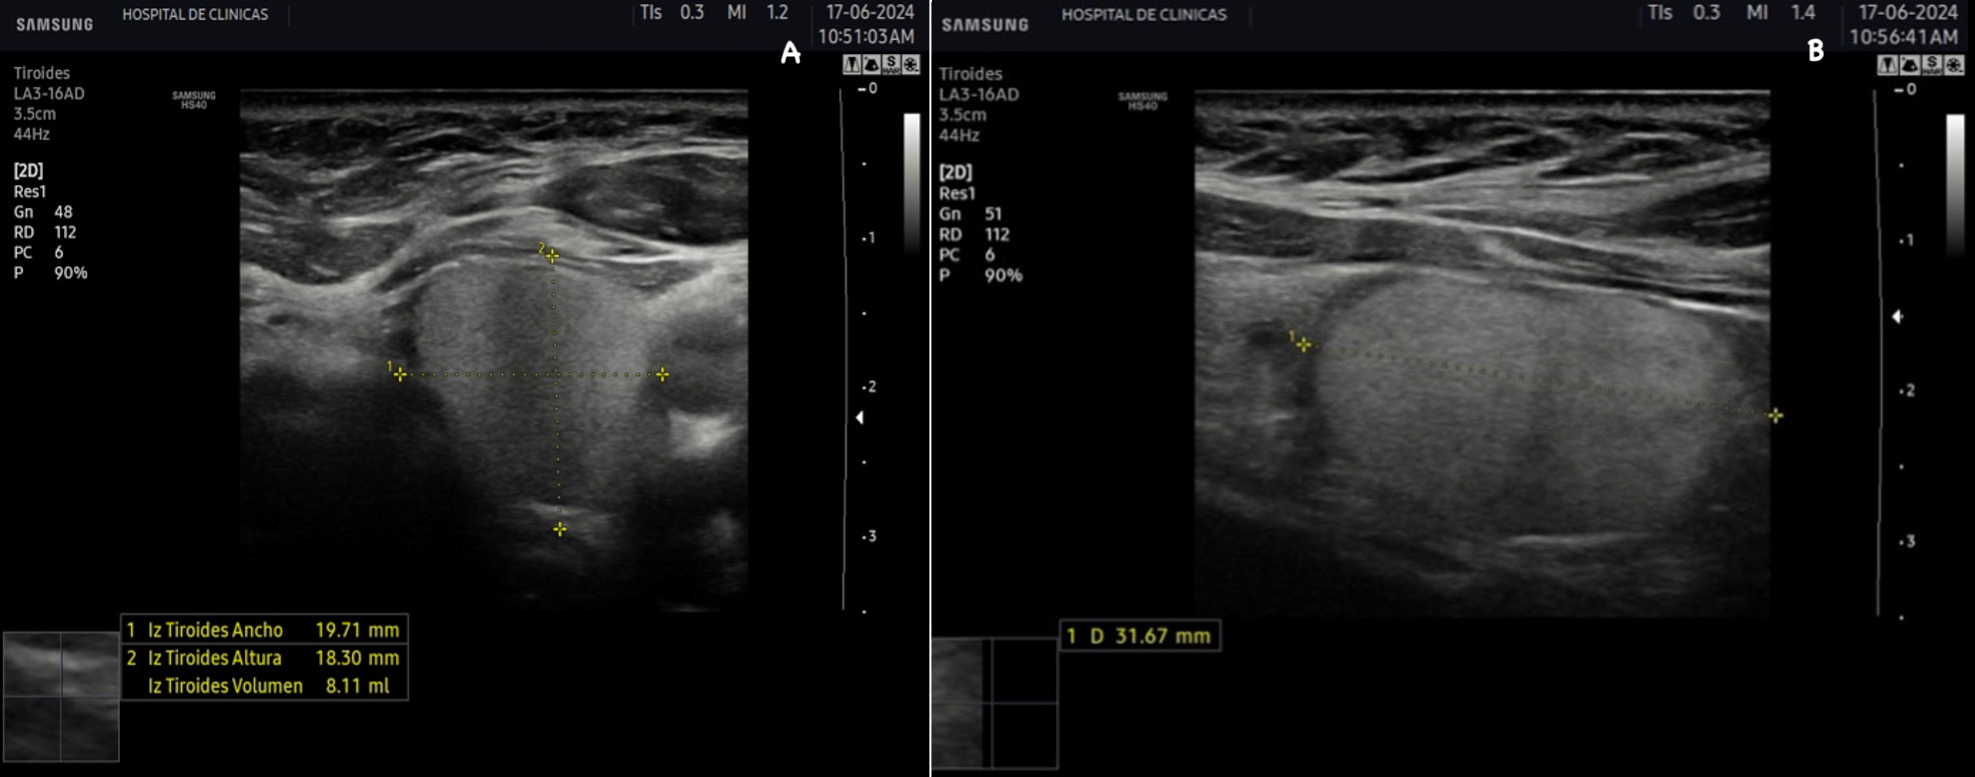

La tiroides de un adulto tiene un tamaño variable de aproximadamente 13 a 18 mm de ancho o transversal (T), 16 a 18 mm de profundidad o anteroposterior (AP) y 45 a 60 mm de largo o longitud (L), el istmo mide entre 2 a 6 mm de profundidad (AP). El volumen del lóbulo se calcula mediante la fórmula V (ml) = 0,479 × AP × T × L (cm). El número 0,479 o 0,524 en la fórmula es el factor de corrección para determinar el volumen de estructuras de una forma elipsoide, existen varias constantes y puede utilizarse cualquiera de ellas. El volumen de la tiroides es la suma de los volúmenes de ambos lóbulos. El volumen del istmo por ser pequeño, en general inferior a 10 mm no está incluido2. El volumen de una tiroides normal tanto en adultos como en niños es fuente de debate. La Organización Mundial de la Salud sugiere un volumen normal en hombres de 7,7 a 25 cm3 y en mujeres de 4,4 a 18 cm3(2). Depende de la edad y el área de superficie corporal de cada individuo2.

La eco estructura es homogénea, los márgenes son regulares y presenta una cápsula ecogénica, su vascularización es escasa. El rango de referencia para una tiroides normal es de entre cinco y diez vasos visibles dentro de la exploración de cada lóbulo valorado con Doppler color2. Se ha descripto que hasta un 50% de los individuos presentan lóbulo piramidal (Figura 3a y 3b). Este sector, en general, es similar en ecogenicidad, homogeneidad y vascularización al istmo y los lóbulos. En la superficie posterior de los lóbulos tiroideos, especialmente en el segmento inferior, puede visualizarse el tubérculo de Zuckerkandl, un ejemplo de este se puede observar en la figura 4a y 4b. Este es un tabique hiperecogénico fibroso que a menudo genera sombra posterior. Se forma por la extensión del tejido tiroideo de las áreas laterales de los lóbulos hacia el sector posterior, y a menudo exhibe una disminución de la ecogenicidad detrás del mismo. Este proceso puede imitar una lesión tiroidea o paratiroidea y causar dificultades en la interpretación2.